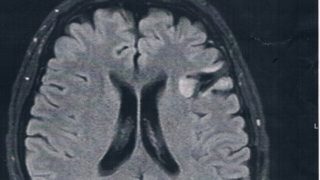

GLIOMA:手術後33ヶ月目の検査

半年ごとの定期検査のために久しぶりに病院に戻った。2014/6/23の覚醒手術から約33か月になる。MRI検査の結果、半年前や一年前と比べても変化は無し!残っている腫瘍は悪性転化していませんでした。まだまだ大丈夫。これからも没問題!今回20...